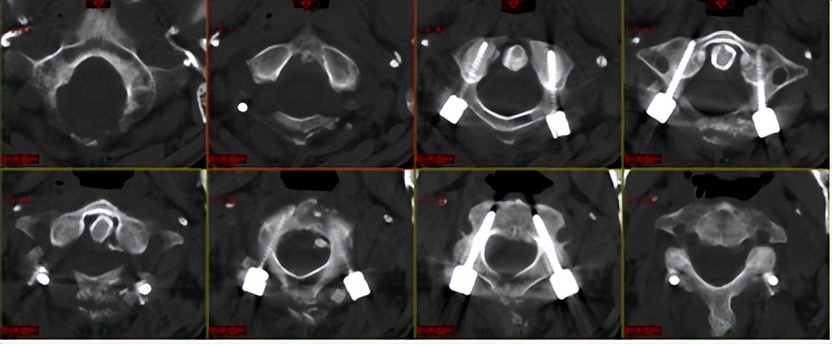

术前神经脊柱外科手术组已经仔细研究,最终制定并实施了“寰椎侧块和枢椎椎弓根螺钉显微置入、寰枢椎脱位矫形复位、后路植骨融合内固定”的手术方案。

由于术前对于患者伤情、解剖学特点和影像资料经过了反复的研究,手术过程非常顺利,神经脊柱手术组医生们以精湛的颅颈椎外科技术,仅以寰枢椎两节段的的置钉内固定,将四枚螺钉精准穿越危险区,箭箭穿心、发发命中,并以严密计算的角度实现精准的微矫形复位,精巧地一次性解决掉了颈椎骨折、延颈髓神经受压、颈椎关节脱位不稳三大难题。不仅实现了颈椎创伤骨折的精准固定和序列重建、解除了脊髓神经的压迫,还完好保留了掌管头颈旋转活动的寰枕关节功能和颈椎旋转屈伸的生理活动功能,手术的成功为后期功能康复和恢复正常生活的可能创造了基本条件。

术后复查:螺钉在椎管和椎动脉孔间狭窄通道穿越而过,并微矫形旋转复位,完美固定